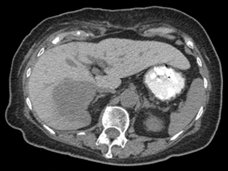

A 71 year-old female presented with an incidental finding of a right hepatic lobe mass, which was hypovascular on contrast-enhanced CT.Images

Axial non-contrast CT (A) and fused PET/CT (B) images through the upper abdomen.